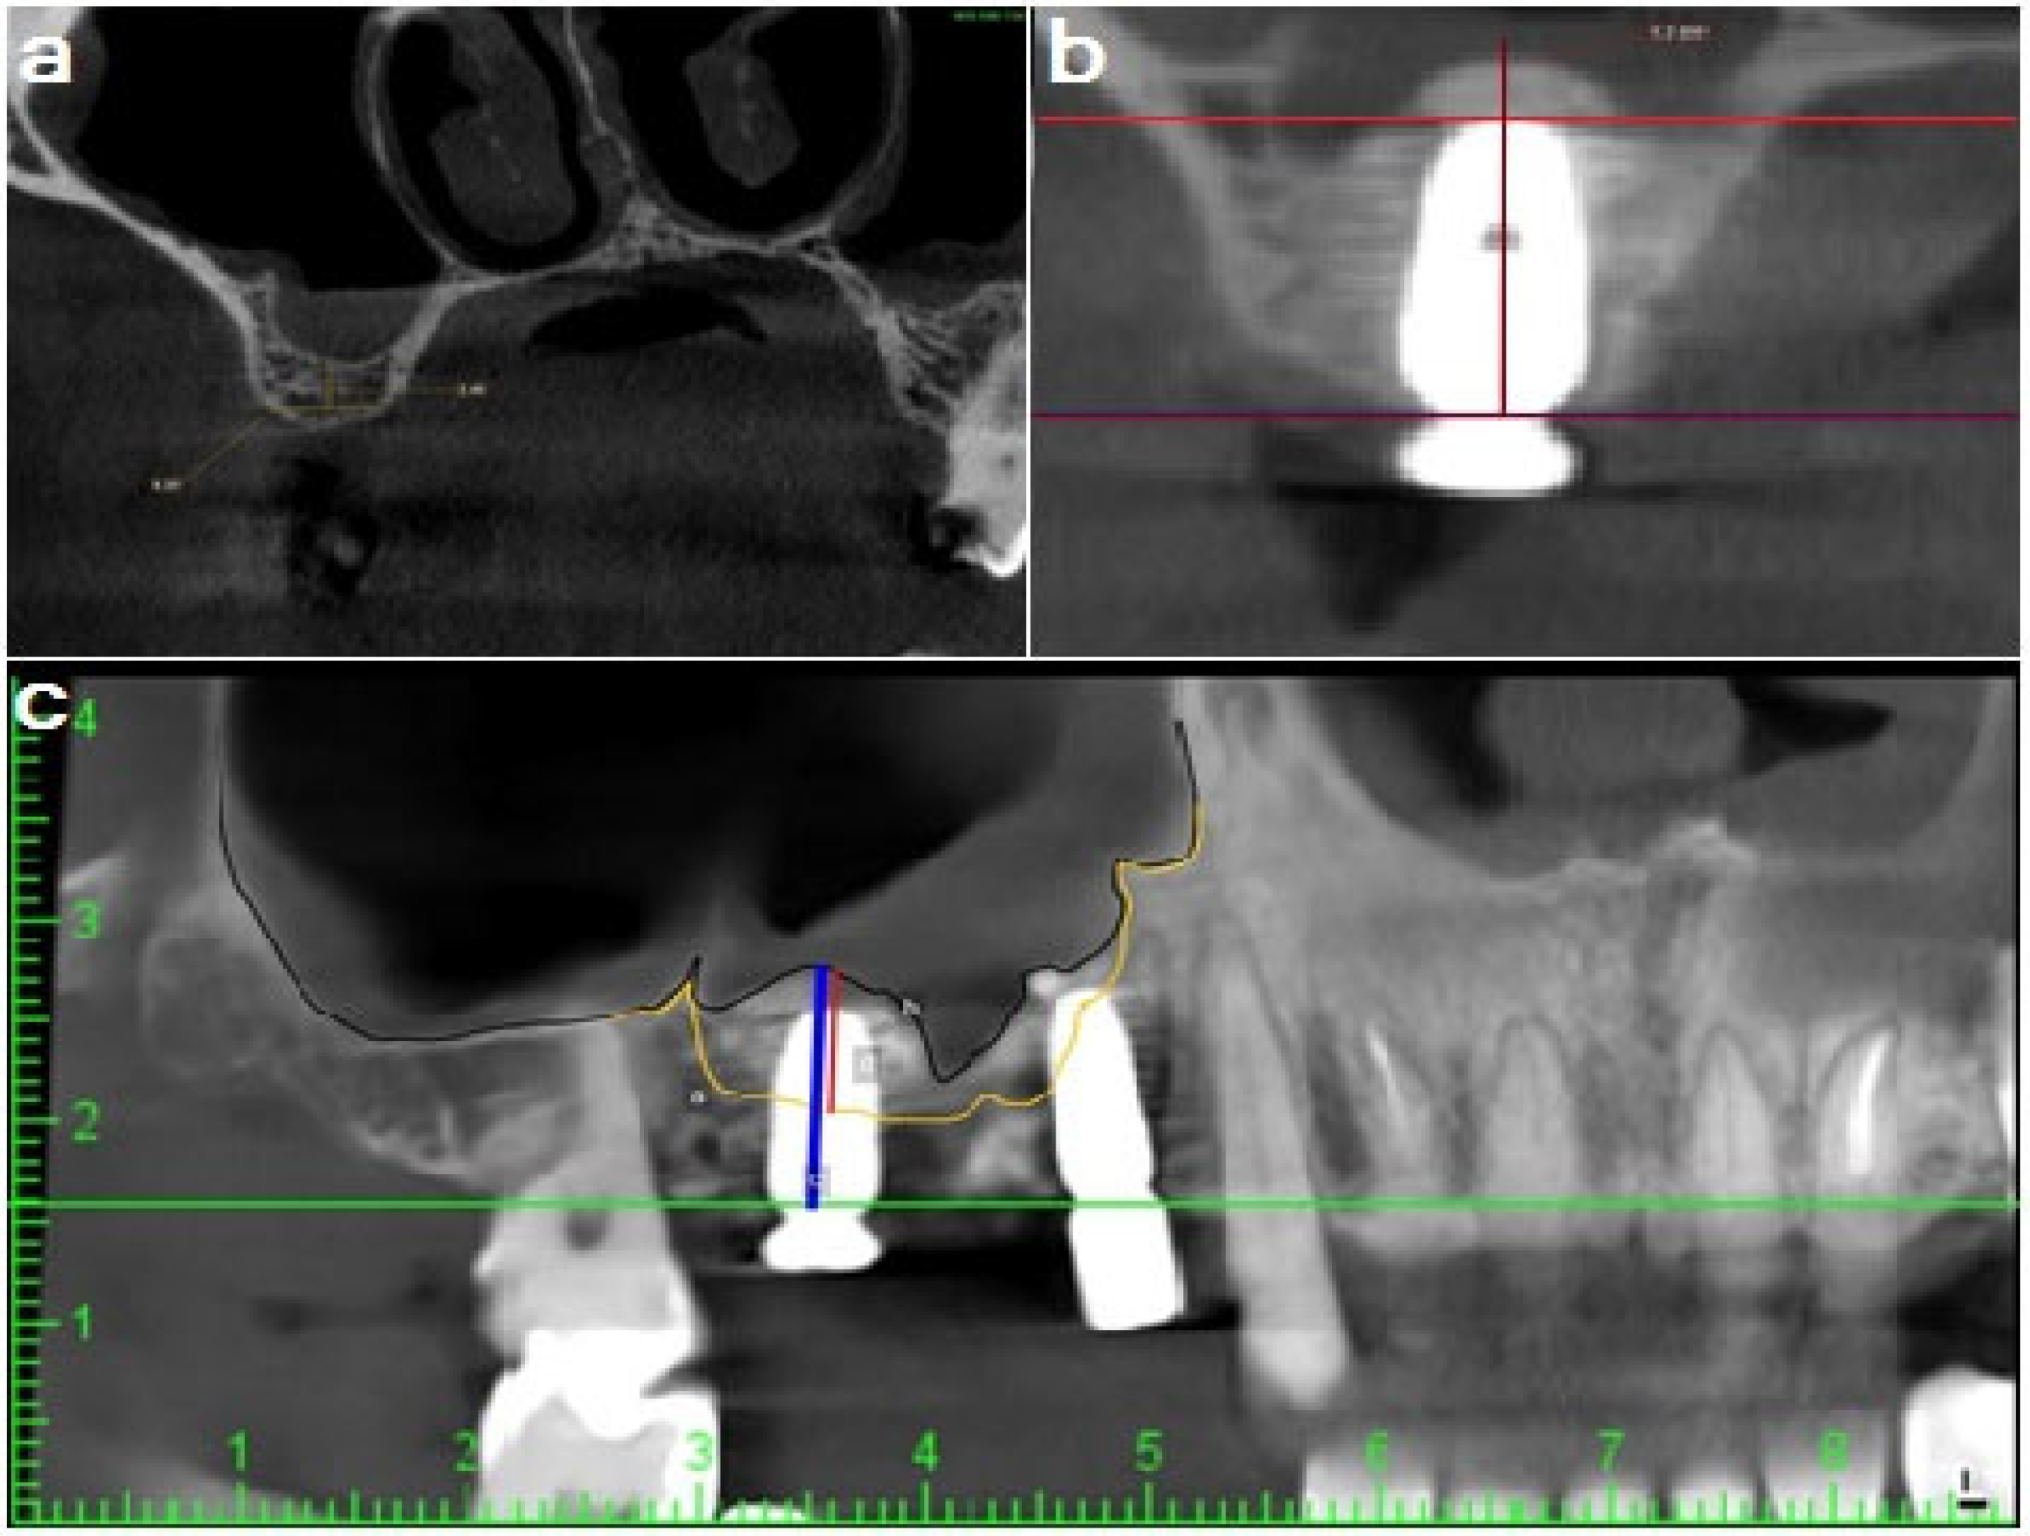

2.9. Radiographic Evaluation

A routine periapical film was performed initially; if the patient met the inclusion criteria, CBCT was performed to evaluate the bone quality and the width and height of the edentulous site. A 3D imaging system (version 5.3.4., Planmeca ProFace®, Helsinki, Finland) captured the target jaw segment with a 5 × 8 cm2 field of view. The CBCT comparison was performed via rigid image registration through the superimposition of two volumes via a matching tool using the software (high precision matching), followed by minute adjustments for precise matching (Figure 5).

2.9.1. Bone Height

After 6 months, bone height changes were evaluated by measuring preoperative residual bone height and distance from the implant platform to the base of the grafted bone at the middle of the implant (Figure 6).

Figure 5. (a1) CBCT volume at 6 months; (a2) preoperative CBCT with identical marks during image registration and (b) superimposition of the two CBCT volumes.

Figure 6. (a) Pre-operative residual bone height; (b) Six-month postoperative CBCT bone height and (c) sinus radiograph showing difference between pre- and postoperative bone height and sinus augmentation.